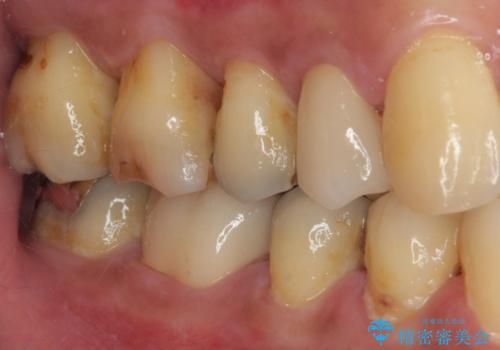

- 銀歯を外して虫歯治療をしたいとのことで来院された患者様です。右下の7番目の歯は銀歯の下に虫歯が広がっており根管治療の可能性もあることを説明したうえで治療を行いました。

左下の5番目の歯はセラミックインレー修復で治療を行うことにしました。

左下の7番目の歯は仮歯に置き換えた後自発痛、咬合痛の所見を認めたので、当院院長である藤巻先生に担当してもらっています。

根管治療後痛みもなくなり快適に使っていただけています。

順次残っている銀歯も虫歯治療を行いながらセラミックに置き換えていく予定です。